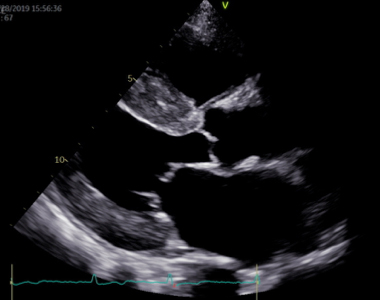

経食道心エコー図検査

経食道エコーでは、経胸壁からではわからないような細かい弁の異常や心内血栓を評価することができます。

近年、心臓外科手術の技術はますます向上しています。先進的な心臓外科手術に、経食道エコーは欠かすことのできない情報を提供するツールです。術前診断として弁の詳細な構造やその機能を評価し、手術デザインに役立てるとともに、手術中も経食道エコーを行って、外科治療の効果を迅速に診断します。

経食道エコーによる僧帽弁逸脱症の診断